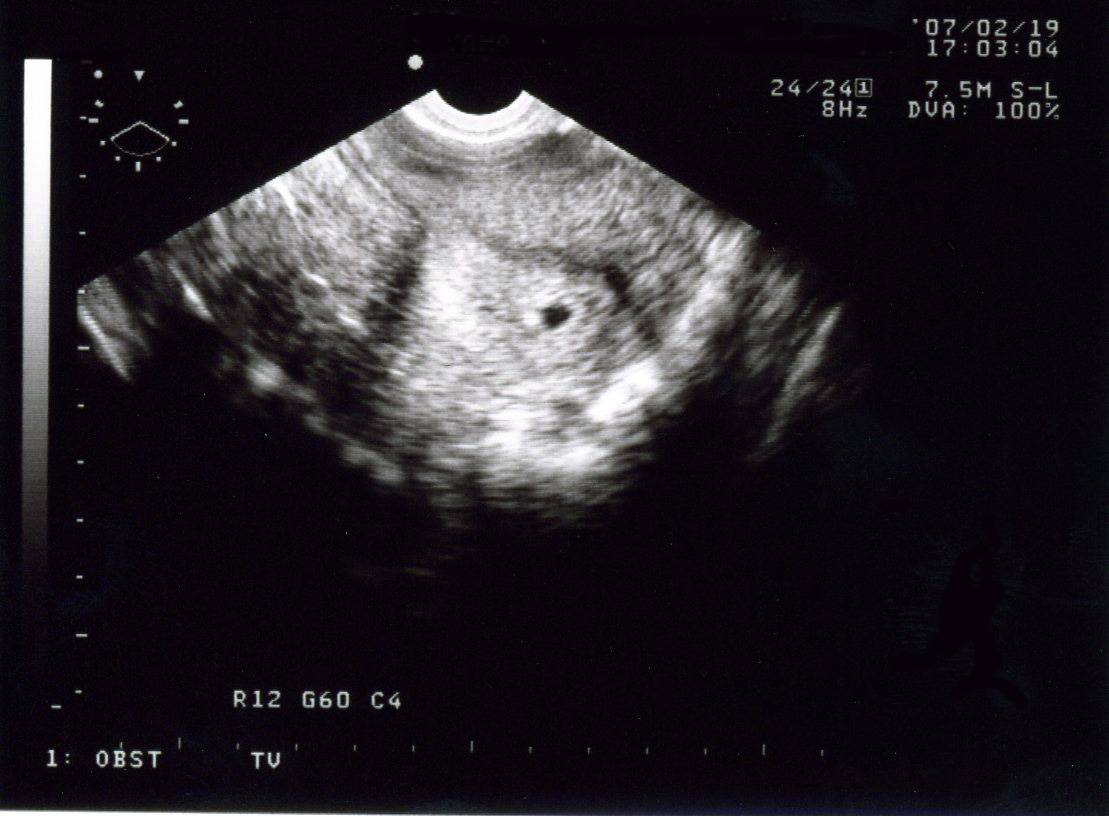

2/19 妻がはじめて産婦人科に検診に行った。

「妊娠はしているらしい。エコーで胎嚢らしいものが写っているけど、小さくて

はっきり確認できないから、10日後か2週間後にまた来て下さいって言われた」

胎嚢を確認できることをちょっと期待して行った妻は少し残念そうだった。

「そうか。でもちゃんと妊娠しているんだからね。おめでとう!」

と私は妻に言った。胎嚢が確認できないと不安なんだろうなぁ。

順調に育ってくれれば、次回の検診では胎嚢が確認できるだろう。

エコーの写真

*真ん中の黒い点が「胎嚢らしきもの」だとのこと